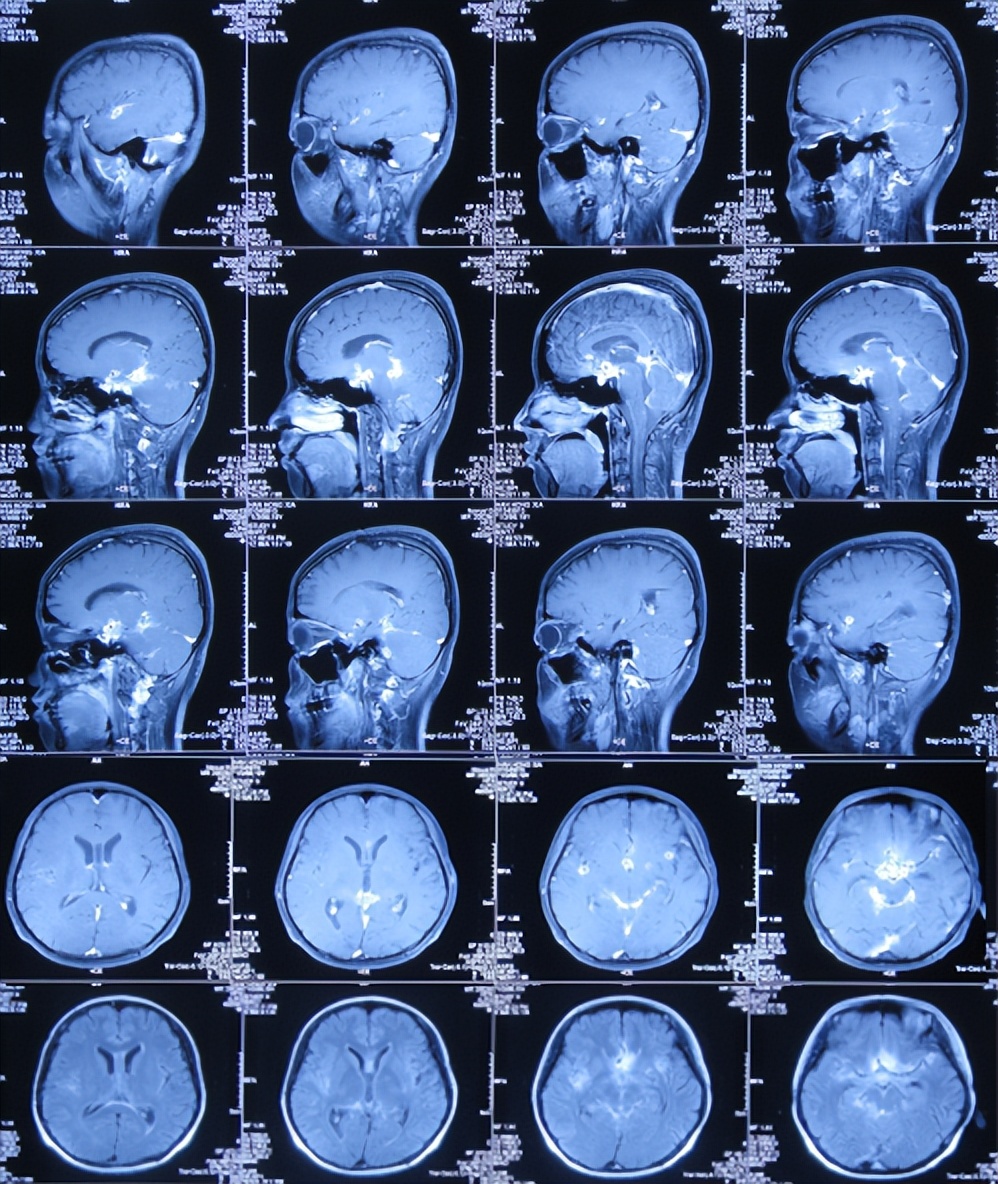

入院治疗78天即2017年8月4日,查脑增强MRI示颅内多发结核脓肿,数量仍多( 图-19 ),继续给予相关治疗。

图-19: 2017年8月4日增强脑核磁